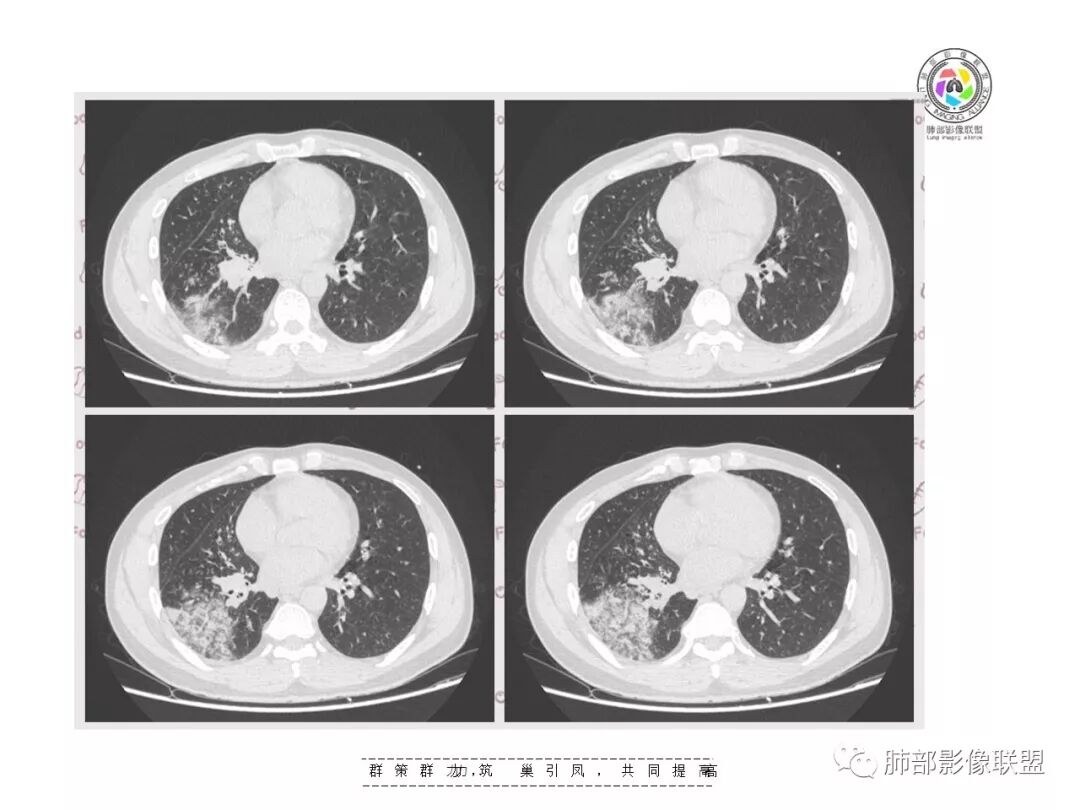

复查胸部CT视频显示肺部病灶明显吸收,淋巴结较前缩小。

患者在本院做了支气管镜,报告是有新生物,取了活检就转院了。病理结果是后来出来的。去肿瘤医院再做支气管镜,病理还是炎症。抗炎治疗(电话追问患者家属,具体不详)一个月后复查,右下肺病变基本吸收,肺门肿块明显变小;纵隔淋巴结基本都没了或者明显变小了

一个月吸收,不是快,是慢,合并机化可能。结核肯定不是。只是觉得你们早上不看病史。有点不好,至少抗感染复查。